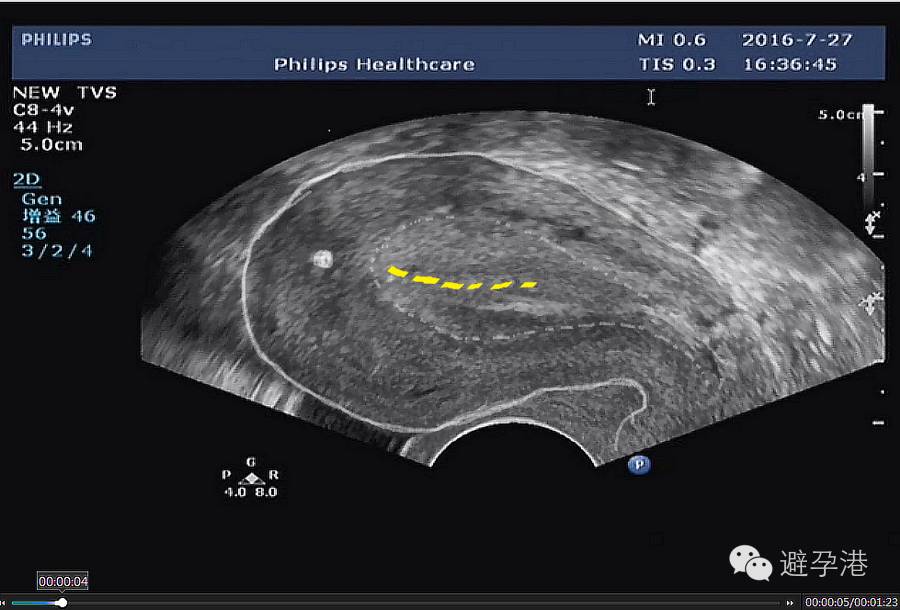

1.吉妮致美是固定式避孕环,放置成功后极少发生脱落下移。超声定位重点在于观察吉妮致美所在位置是否安全,即观察吉妮致美第一个铜套上缘到子宫浆膜层的(S-S)距离。

吉妮致美环怎么样吉妮致美节育器超声图像解读_https://www.jmylbn.com_新闻资讯_第8张

吉妮致美环怎么样吉妮致美节育器超声图像解读_https://www.jmylbn.com_新闻资讯_第9张

①S-S≤1.1cm,为避免吉妮致美异位,请将之取出。

S-S在1.1~1.4 cm之间,请扫描吉妮致美线结在子宫肌壁间位置,安全的位置应该是在内膜线与浆膜之间;如线结与浆膜重叠,或线结距浆膜<0.2 cm,请取出。

③S-S在1.4~2.2 cm之间为安全距离。